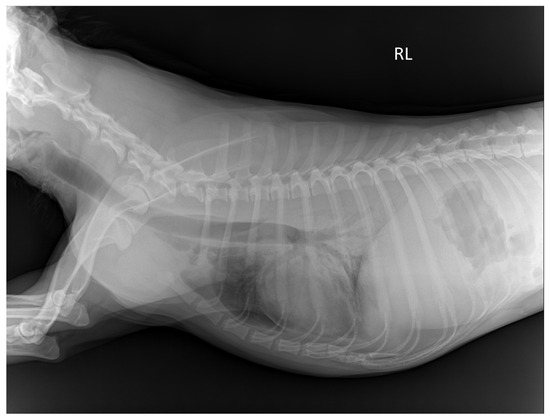

On the thoracic image, the visibility of the trachea and proximal bronchi, descending aorta border, upper and lower endplates of the thoracic vertebrae, cardiac border, costophrenic angles, and lung parenchyma were rated (Figure 1). Radiologists assessed the visibility of the spinous process of the lumbar spine, outline of the cranial and caudal poles of the left kidney, and outline of the urinary bladder in the abdominal area.

Figure 1.

Radiographic image of the thorax of a TS cadaver 12 weeks post-embalming. RL: Right lateral recumbency. The mean score for thorax is 1.58; trachea and proximal bronchi is 2; descending aorta is 0.5; endplates of thoracic vertebrae is 3; cardiac border is 2; costophrenic angle is 1; and lung parenchyma is 1. The scores were assigned as follows; 0 = not visible, 1 = poorly visible, 2 = adequately reproduced, 3 = excellent reproduced.